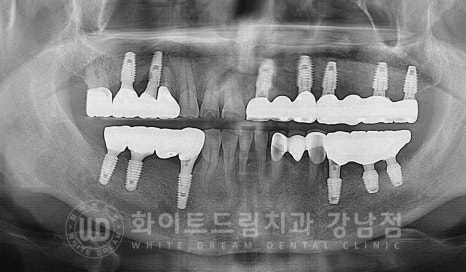

23.01.30, 5개월 만에 최종 보철을 체결하고 교합 체크 과정을 받으면서

치료를 마무리했답니다.

동일 인물이며 동일 환경에서 촬영됨

치료 기간 : 23.08.19 - 24.02.29